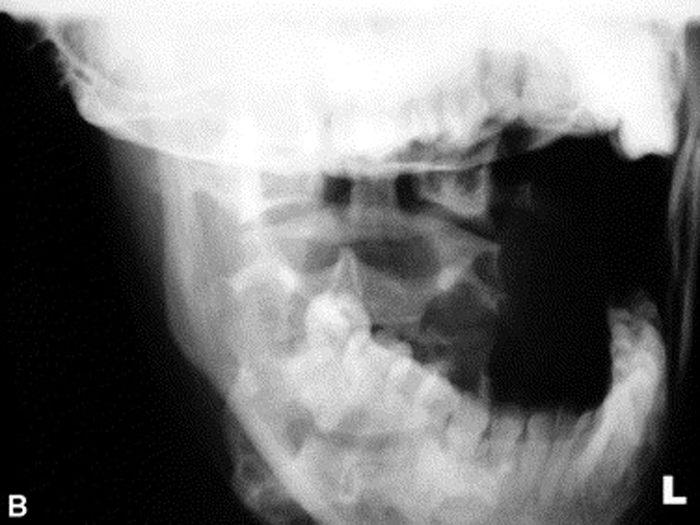

Radiographs were ordered (Figure 1, A through C) due to the longevity of the complaint and revealed a persistent narrowing of the left para-odontoid space. The radiology report stated that the asymmetry might be due to a right rotational malposition of atlas, possibly a compensatory response to a left rotational fixation of axis.

Figure 3.

C: Neutral and angulated anteroposterior open month

radiographs reveal a narrowed left para-odontoid space.